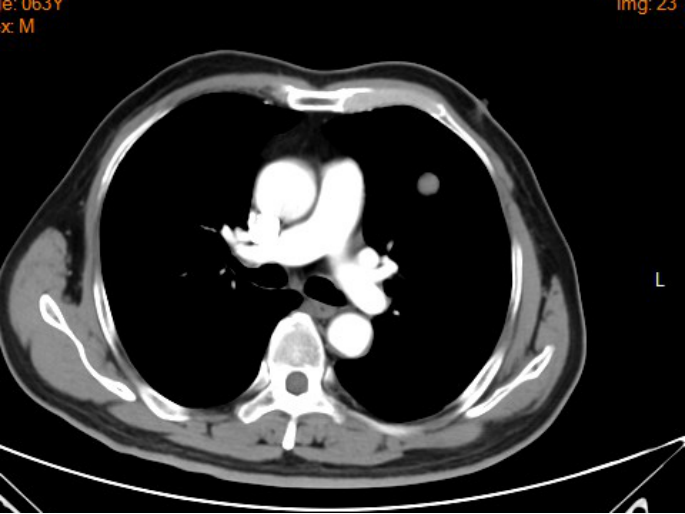

影像学资料:

2017年3月

2017年7月

2018年2月

2018年3月